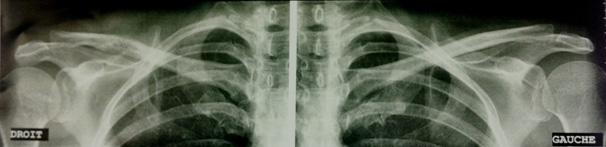

Madame P., âgée de 47 ans, vous consulte pour une douleur de l’épaule droite avec impotence fonctionnelle totale. A l’examen, vous retrouvez une déformation de la clavicule et vous rapportez rapidement la symptomatologie clinique à un problème lié à cet os. Vous demandez une radiographie standard.

On constate une lésion du tiers externe de la clavicule droite, que vous faites agrandir.

Cette lésion